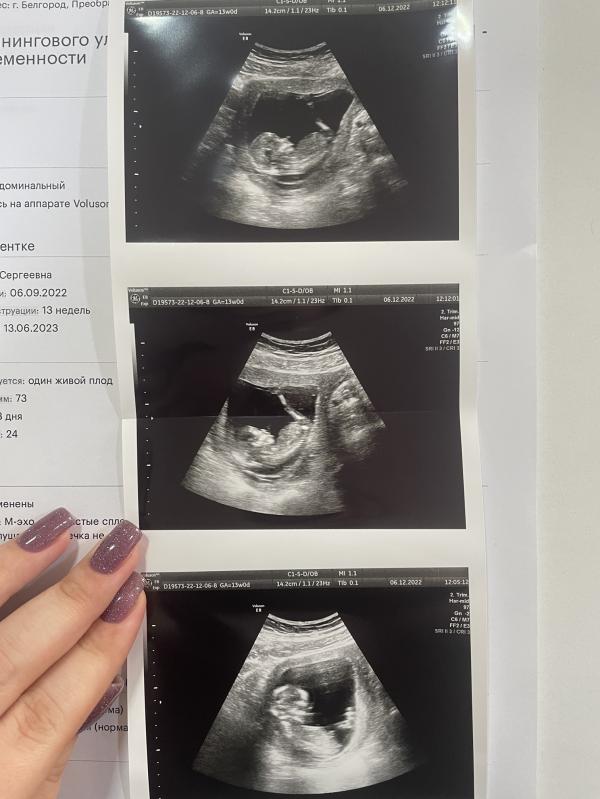

Ровно 13 недель❤️

И у меня сегодн скрининг был и не сказали😥